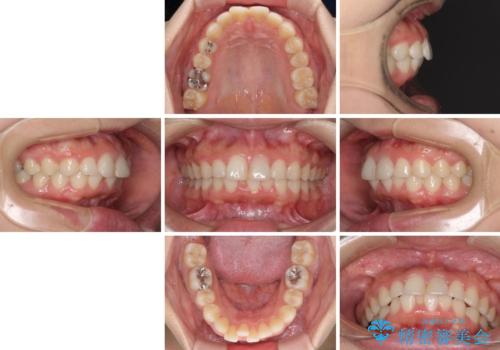

- 以前の矯正治療の後戻りを気にして来院された患者様です。

下顎前歯にデコボコがあるため、ワイヤー矯正により改善することとしました。

もう少しデコボコを改善したかったのですが、ご本人の希望もあり、装置を除去しました。

後戻りを防止するため、舌側を細いワイヤーによる保定を行いました。